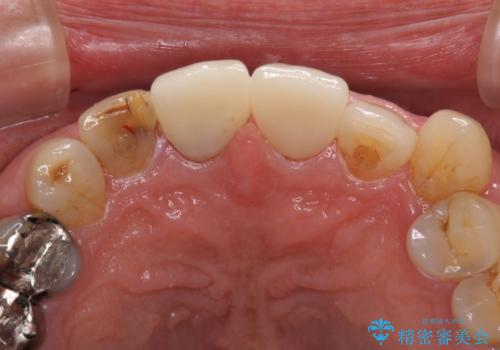

差し歯(被せ物)のやりかえ 上の前歯で印象が明るく

- 前歯がぐらつくことを主訴にご来院された患者様です。ご本人は抜歯と考えており、インプラント以外の治療をご希望でした。しかしながらぐらついていた原因は、古い差し歯が取れかけていたことでした。

遠方から通院されること、仕事上短期間で治療したいとのことを考慮して、残っている歯はかなり小さいものの、保存すべきと判断して当日処置から行いました。

西日本から新幹線でご来院された患者様です。前歯は都内の医院でやりたいとのことで、はるばる通院してくださいました。通院回数が最小限になるよう工夫しました(1回あたりの時間は長くなります)。

残っている歯が小さいと、差し歯はぐらつきやすくなりますが、その形態によっては抜歯を回避できることがあります。